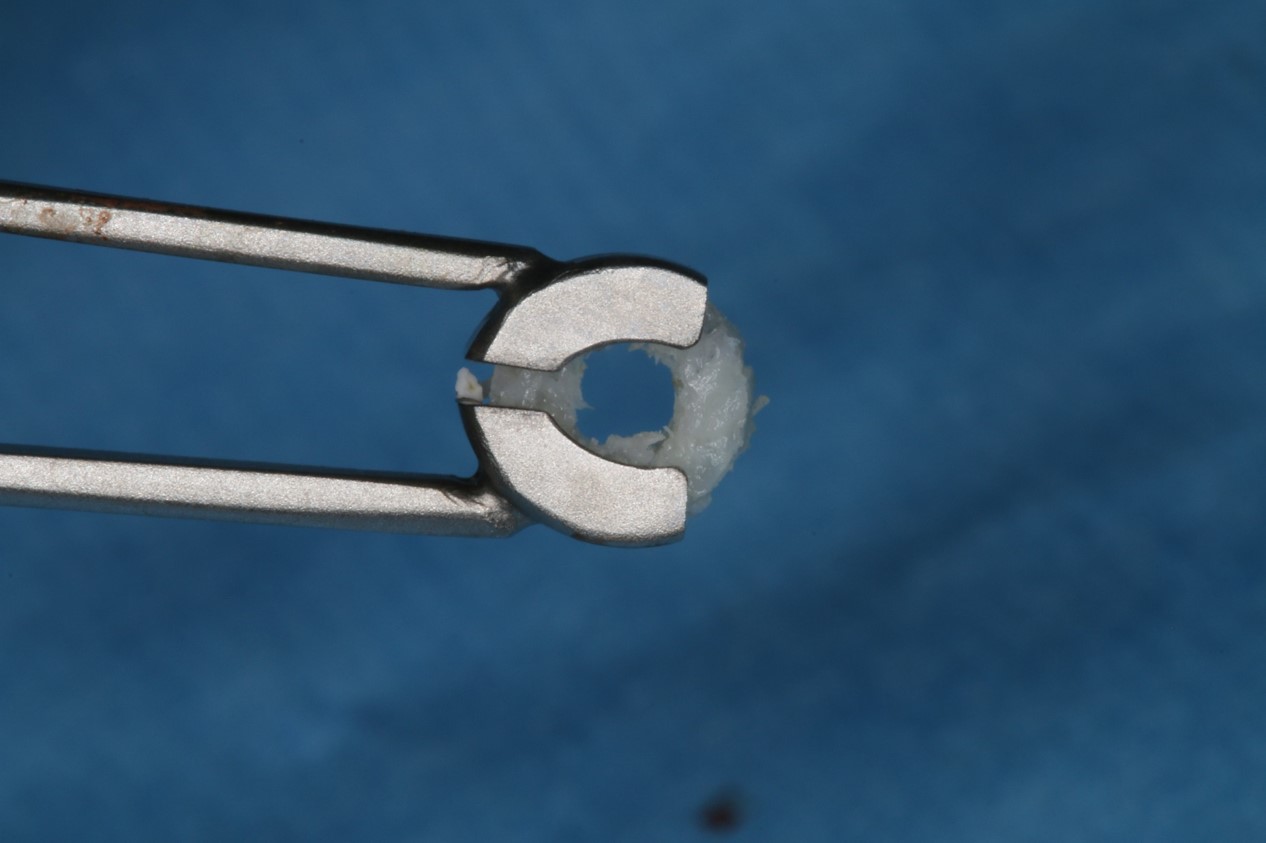

Periimplantitis treatment with maxgraft® bonering - Dr. B. Giesenhagen

Severe periimplantitis at tooth 15 with bone loss up to 1/3 of the implant